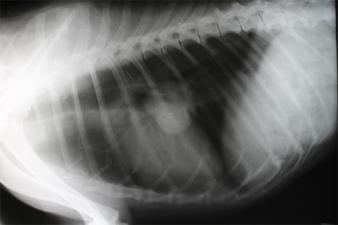

Primární nádor plic

Rakovina plic se výrazně častěji vyskytuje u starších psů. Není výjimkou, že se na rakovinu přijde spíše náhodou, například u pravidelného vyšetření zdravotního stavu či kontrolního rentgenu. Pokud je zjištěn pouze jeden nádor, doporučuje se podstoupit chirurgický zákrok. Ačkoli se jedná o invazivní zásah do těla zvířete, pes se celkem rychle zotavuje a komplikace nejsou příliš časté. Pokud je v době diagnózy patrné rozšíření rakoviny, je vhodné podstoupit chemoterapii a zabránit tak šíření do dalších částí těla.